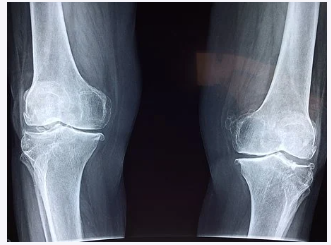

보스웰리아 효능에 있어서 가장 주된 효과는 관절 건강입니다. 다른 것보다도 관절에 굉장히 좋습니다. 이 안에는 ‘보스웰릭산’이라는 항염작용을 하는 성분이 들어있는데요. 이 ‘보스웰릭산’이 관절염을 개선시켜주어 관절 건강에 좋은 것이죠. 그래서 특히 관절염으로 고생하시는 분들이 자주 섭취하곤 합니다.

연골은 재생이 불가능하기 때문에 관리를 잘 해줘야 하는데요. 연골은 70%가 소모 돼도 인지를 잘 못한다고 합니다. 만약 통증이 느껴지면 그때는 이미 70%이상 진행이 된 것이죠. 그러므로 미리미리 관리를 해줄 필요성이 있습니다.